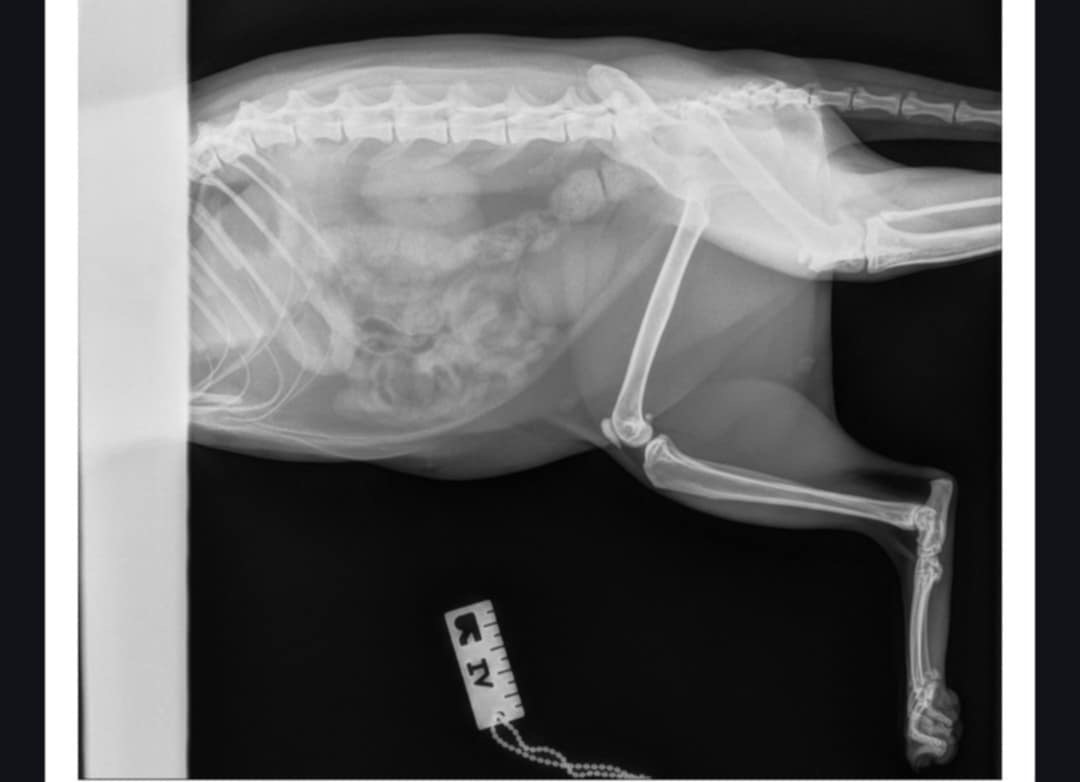

Regrettably, Simba has sustained a fracture on his back left knee and requires surgical intervention. The estimated cost of the surgery ranges from $8,000 to $10,000, contingent upon the specific procedure to be performed. Any donation would mean the world and help Simba and our family.